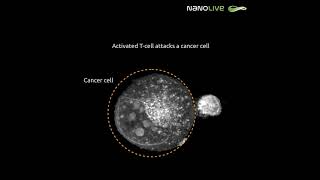

Using microwaves to destroy cancer cells (3D Animation) Activated T cell attacks a cancer cell

Activated T cell attacks a cancer cell Macrophage eating Cancer Cell 3D Animation | Phagocytosis | Immunology @biologyexams4u

Using microwaves to destroy cancer cells (3D Animation) Activated T cell attacks a cancer cell

Activated T cell attacks a cancer cell Macrophage eating Cancer Cell 3D Animation | Phagocytosis | Immunology @biologyexams4u